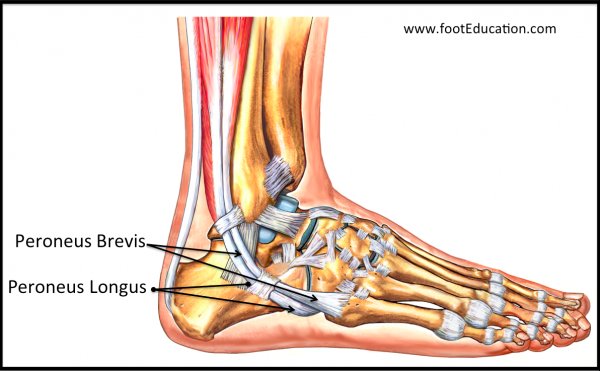

족부에만 40개 넘는 부골이 생길 수 있습니다. 부골이란 것은 대부분 2차 골화중심이 유합되지 못한 채 유지되는 상태로 성장이 끝나게 되면 다음과 같은 작은 형태의 뼈 모양으로 남게 됩니다.

Os vesalianum 이나 Iselin disease(traction apophysitis) 등을 함께 감별을 해주어야 합니다.

Tibialis posterior가 붙는 내측에 위치하는 배모양의 주상골에서도 부골이 있어 통증이 있는 경우도 있습니다.

이러한 부골은 증상이 없을 경우 수술을 할 필요가 없는 뼈들입니다. 정상적인 변이라고 볼 수 있는 뼈들이기 때문이죠.

대부분 보존적인 치료를 하며, 통증이 심하거나 생활에 지장이 있는 경우 부골 제거술을 시행해 볼 수 있습니다. (부착된 인대 들도 함께 제거될 수 있으므로, 수술시 인대 부분의 생역학을 잘 고려해야합니다.)